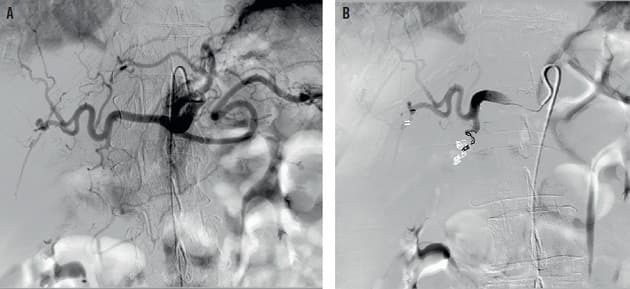

A. Fremstilling af truncus caeliacus, foretaget på makrokateter med spidsen i truncus. B. Efter coiling i a. gastroduodenale foretaget via mikrokateter i a. hepatica communis.

Til trods for udbredt anvendelse af syrepumpehæmmere, eradikationsbehandling af Helicobacter og endoskopisk behandling er øvre gastrointestinal blødning forårsaget af gastroduodenale sår fortsat en hyppig og alvorlig tilstand. I statusartiklen gennemgår Rasmussen et al transarteriel embolisering, hvor man først identificerer den blødende arterie ved en CT-angiografi og efterfølgende foretager en selektiv kateterisation gennem a. femoralis med henblik på embolisering.